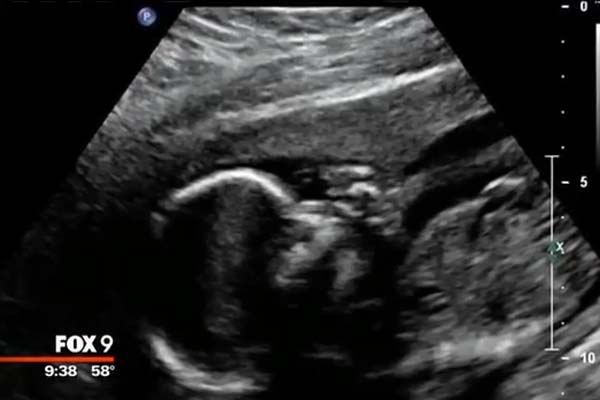

Беременность проходила как обычно и маленький Ноа вот-вот должен был появиться на свет.

Во время беременности пуповина Ноа оказалась зажатой во время внутриутробного развития и из-за этого плод родился мертворожденным. Это событие было год назад, но Валари продолжала хранить у себя детскую кроватку, это была единственная память о её малыше, который покинул её не успев появиться на свет